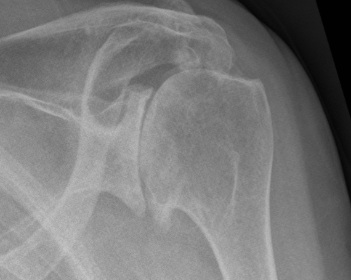

Differential diagnosis

Cuff arthopathy

- proximal migration of head

- subacromial sclerosis / acetabularization of acromion